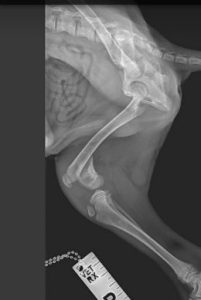

Jamie and his two siblings were found abandoned in a derelict school house. Desperation was etched on their sweet faces and their bodies were full of fleas and their skin covered in demodex. Jamie was found to be less active than his siblings and after x-rays was found to have a fractured femur. He has now had an operation and is recovering from his ordeal alongside his brothers